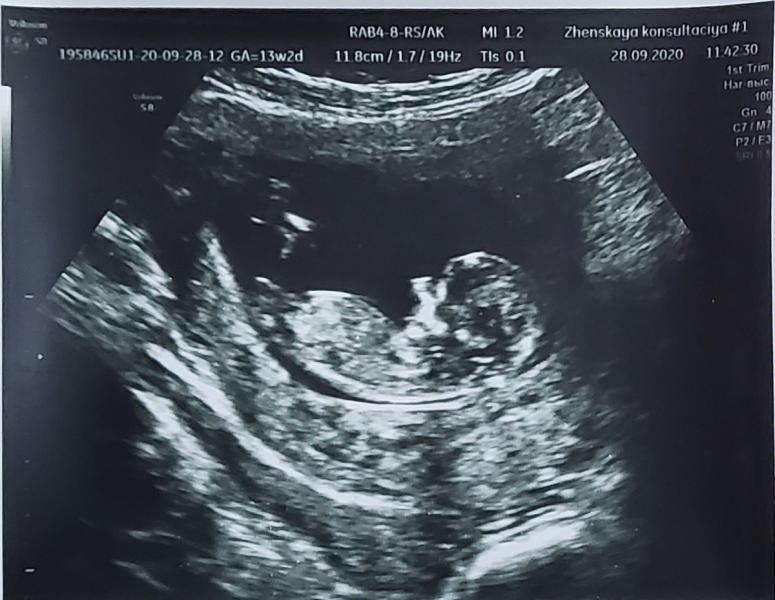

Всё хорошо с нашей малышкой! Ножками-ручками машет, такая милота! 😍

Была 4 дня назад на узи, смотрели по животу, все ок было.